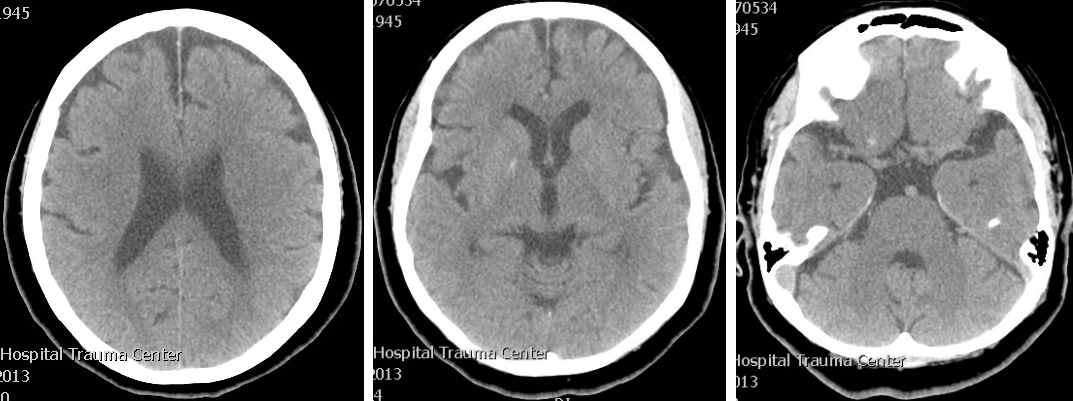

This is the case of a 57-year-old Indian right-handed woman who was known to have hypertension and ischemic heart disease and was on regular medication for these comorbids. On the day of presentation she woke up well and after 2 waking hours she started having involuntary movements on the right side of the body. This occurred 5–7 times and was described by the patient like some tightening spell which would persist for 5–10 sec and then it relieved by itself. This was followed by a weakness on the right side of the body which was so severe that she could not move out of bed. After half an hour the weakness started improving. When she reached hospital, her condition had much improved. On examination she was mildly slow in mental processing, but GCS (Glasgow Coma Scale) score was 15/15. She had mild dysarthria but speech assessment and cranial nerves were normal. In the motor system she had mild weakness with power of grade 4+/5 in the right sided limbs, both proximally and distally, and mild hypotonia on the right side. Power on the left side was normal. Reflexes were normal and symmetrical on both sides. The other examination results was unremarkable. We did CT brain which was normal (Figure 1 [Fig. 1]). Preliminarily we thought of tonic seizure disorder followed by Todd’s paralysis because we did not witness that episode and were dependant on history. We thought of stroke/transient ischemic attacks and discussed it with the family. At that time deficit was minimal and history was also suggesting Todd’s paralysis, so the unanimous decision was made not to treat as stroke and just to observe for seizure. Therefore she was not given thrombolytic therapy, however we loaded her with 300 mg Aspirin.

CT brain was repeated and was normal. EEG was normal. Laboratory investigations were normal except of the high cholesterol level. MRI brain showed infarction in the area of the left internal capsule, the putamen and some part of the thalamus (Figure 2 [Fig. 2]). Echocardiography and carotid Doppler were normal.